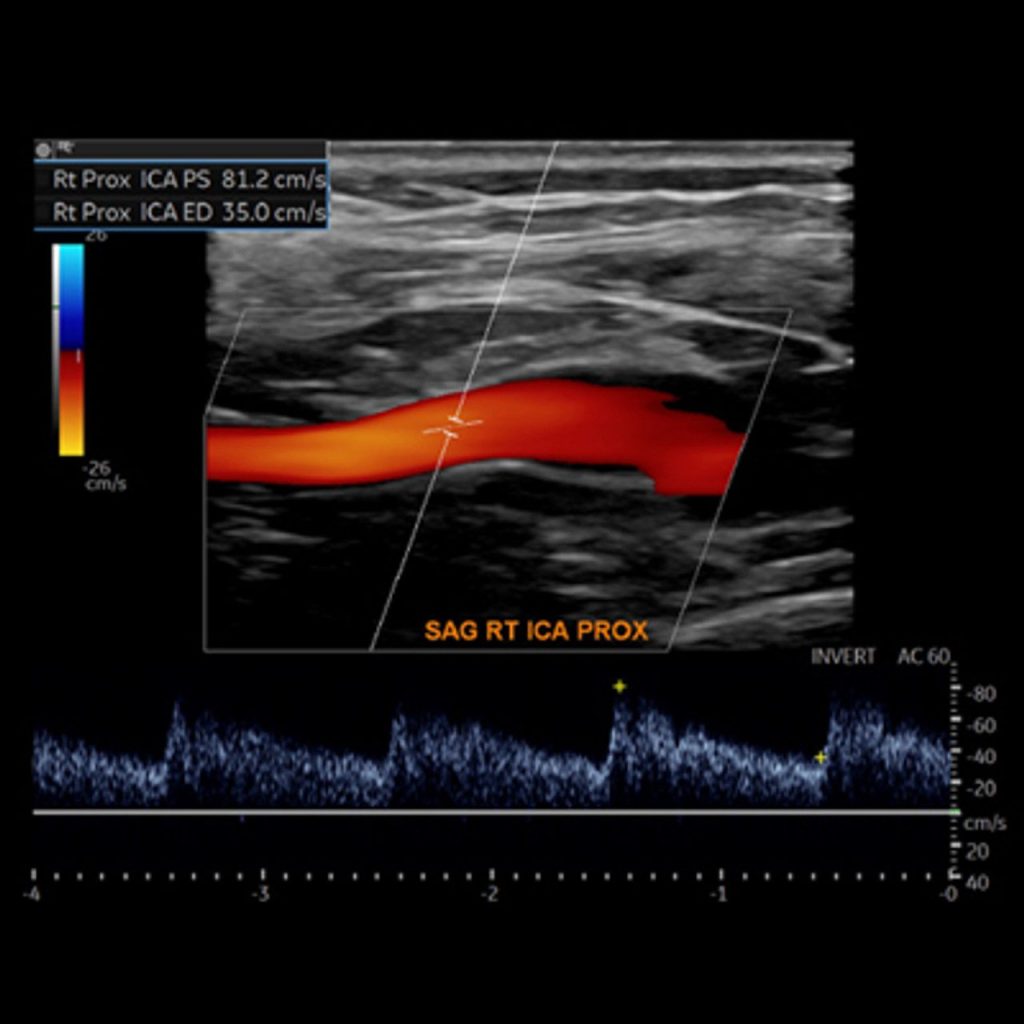

• Basics of the Carotid Duplex Examination and Criteria for Diagnosis of Internal Carotid Artery Stenosis

• Use grayscale imaging, color Doppler analysis, and spectral Doppler waveforms to assist in the diagnosis of arterial and venous disease

• Apply interpretation skills for diagnosis of internal carotid artery stenosis using duplex ultrasound